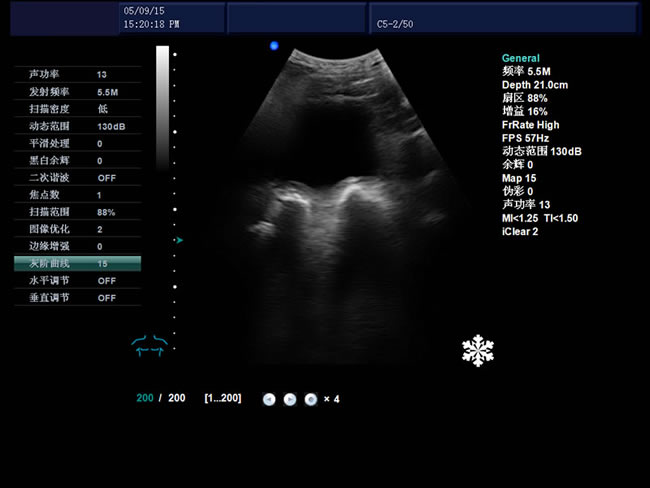

S8 彩色多普勒獸用超聲診斷儀

• S8彩色多普勒獸用超聲診斷儀是徐州市大為電子設(shè)備有限公司推出的一款全新的彩色超聲診斷儀器。

適用范圍:B超機(jī)產(chǎn)品性能

高集成數(shù)字式彩色多普勒技術(shù)

寬頻探頭,頻率范圍從2.0MHz到10.0MHz